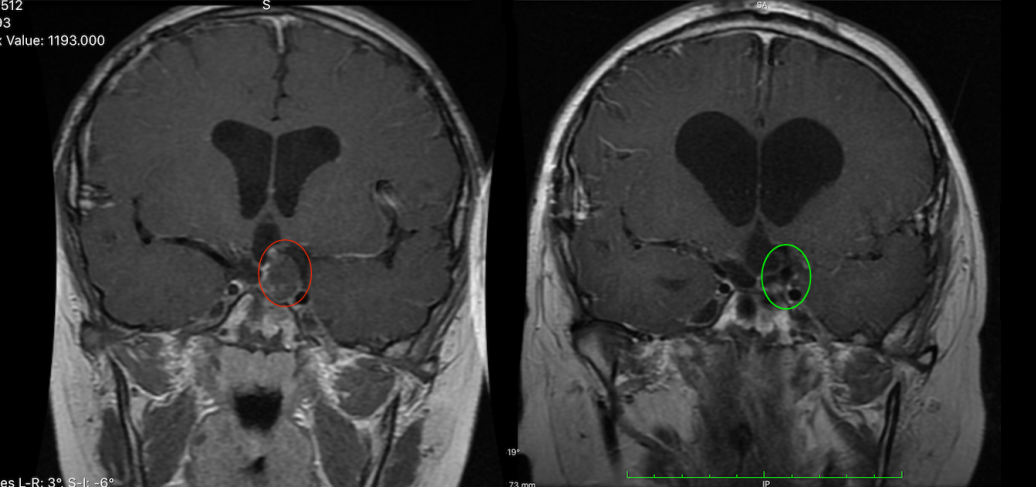

术前术后MRI对比,红色为术前肿瘤位置,绿色为术后切除效果